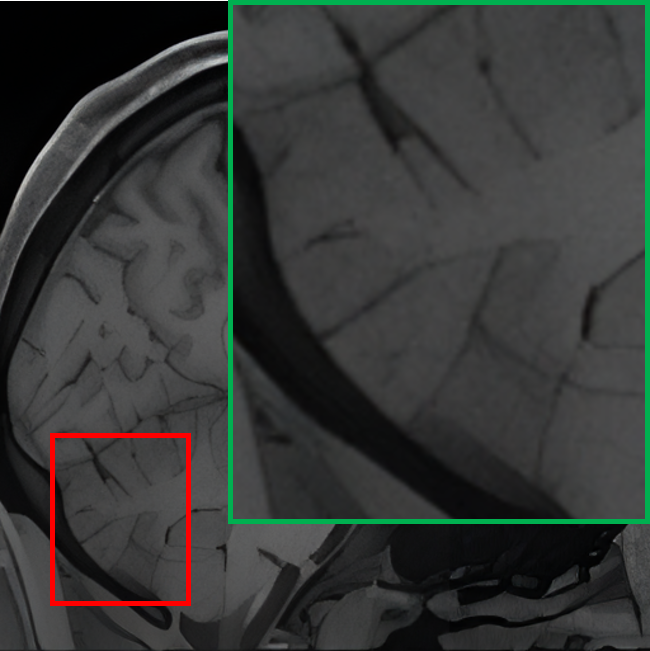

IV-B1 Qualitative visualization analysis

Table II provides a visual comparison of 7T-like MRI generated by various State-Of-The-Art (SOTA) SR methods using 1.5T MRI as input. The compared methods include ESRGAN [43], SR3 [26], and our proposed baseline (teacher) model. To facilitate a focused and intuitive assessment, the cerebellar region, known for its intricate structure and HR requirements, is specifically selected for comparison. To comprehensively evaluate the methods, T1w and T2w slices from both the axial and coronal planes are displayed in an alternating interleaved format, which highlights each method’s effectiveness across distinct anatomical views and tissue contrasts, allowing for a clearer assessment of their ability to capture fine structural details. The comparison reveals that ESRGAN enhances the resolution but introduces significant artifacts, where unnatural patterns distort the anatomical structures. While it provides some sharpening, the output deviates substantially from the ground truth. SR3, on the other hand, prioritizes smoothness, leading to blurred outputs that fail to recover fine details and textures, which results in a loss of critical anatomical information. In contrast, the proposed teacher model excels in preserving fine structural details and reconstructs intricate anatomical features without introducing artefacts or excessive blurring, demonstrating superior performance compared to ESRGAN and SR3 in both visual quality and alignment with the 7T ground truth. Additionally, the comparison highlights a consistent discrepancy in SR performance between T1w and T2w images. T2w images generally exhibit inferior reconstruction quality, which can be attributed to their inherently lower SNR and higher susceptibility to magnetic field inhomogeneities. These characteristics pose significant challenges for SR models, making accurate reconstruction more difficult. Despite these challenges, our proposed model consistently outperforms ESRGAN and SR3, delivering superior results for both T1w and T2w imaging.

TABLE II: Qualitative visualization comparison with SOTA models

Input (1.5T) Ground Truth (7T) ESRGAN SR3 Ours (Teacher)

T1w

[Uncaptioned image] [Uncaptioned image] [Uncaptioned image] [Uncaptioned image] [Uncaptioned image]

T2w